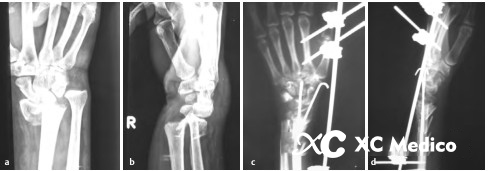

13. Используйте внешние фиксаторы для обработки обожженных переломов дистального радиуса. Внешние фиксаторы подходят для тяжелых переломов дистального радиуса, сопровождаемого огромным отеком, открытыми переломами или местными кожными условиями, которые не позволяют внутреннюю фиксацию (например, фиксацию пластин) (рисунки AD ниже).